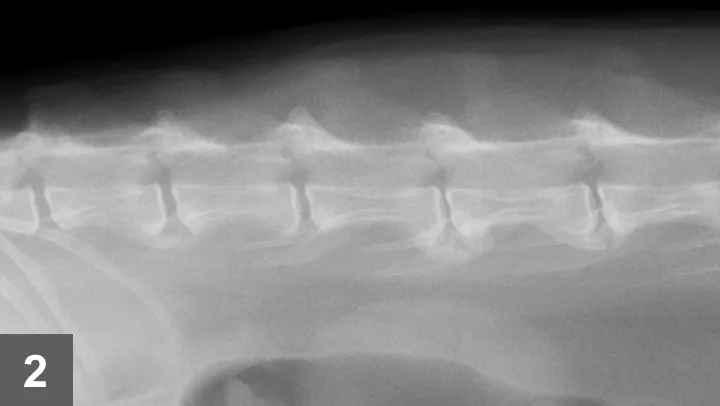

For conclusive proof of osteoarthritis, look for radiographic signs supportive of the loss of articular cartilage, osteophyte formation, bone remodeling, and inflammation along with cytology of joint fluid showing increased inflammatory cell counts and protein levels and decreased viscosity of fluid (see Laboratory Findings/Imaging for further discussion). Spondylosis deformans is diagnosed radiographically by identifying bony spurs of the fibrocartilagenous intervertebral joints of the spine (Figures 1 and 2).

• Radiographs of DJD will depict bone spurs, osteophytes, joint surface lucencies, or narrowed joint space reflecting loss of articular cartilage. There is generally no increase in volume of joint fluid associated with degenerative conditions; however, joint space may be wider than normal if severe inflammation is present.